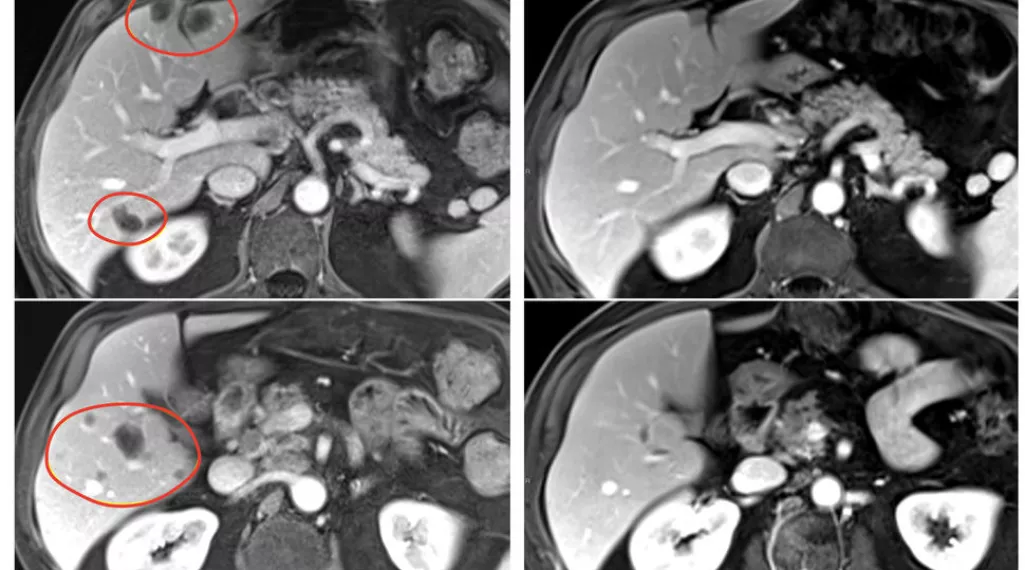

Patients in the clinical trial, who had a variety of gastrointestinal tumors, also received the immune checkpoint inhibitor pembrolizumab (Keytruda) to help further boost their immune response. The result was nearly 24% of patients treated with selected TILs plus pembrolizumab had a substantial reduction in the size of their tumors, compared with 7.7% of patients who received selected TILs without pembrolizumab. Patients treated with TILs that had not been selected for anti-tumor activity had no tumor shrinkage.

The clinical trial included 91 patients with metastatic gastrointestinal cancers — including esophageal, stomach, pancreatic, colon, and rectal cancers — that had worsened despite a median of four prior treatment regimens. In the pilot phase of the trial, 18 patients were treated with TILs that had not been selected for anti-tumor activity, and there were no objective responses (tumor shrinkage of at least 30% is considered an objective response). In the second phase, 39 patients were treated with selected TIL therapy, and three (7.7%) had objective responses.

In the third phase, 34 patients received pembrolizumab immediately before selected TIL therapy to prevent the newly introduced immune cells from becoming inactivated by the patient’s own immune system. This group had the best response, with 8 of 34 (23.5%) patients experiencing an objective response. All 91 patients had also received standard chemotherapy and high-dose interleukin-2 before the TIL therapy.

In the trial’s second and third phases, objective responses were seen in multiple types of gastrointestinal cancers, including cancers of the colon, rectum, pancreas, and bile duct. Responses lasted between 8 months and more than 5.8 years in the group that received selected TIL therapy alone, and between 4 months and 3.5 years in the group that received selected TIL therapy and pembrolizumab. Serious side effects occurred in 30% of patients treated with selected TILs.